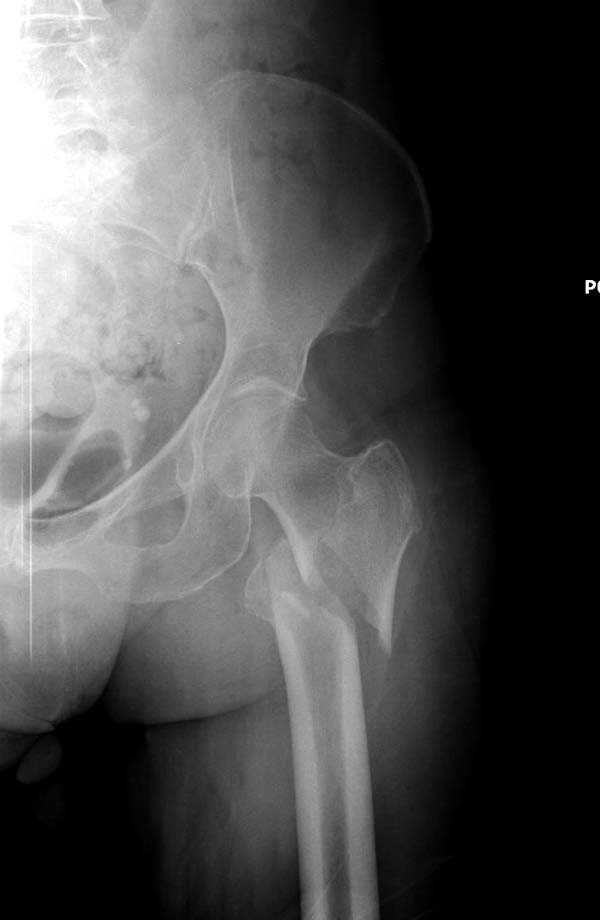

Здесь представлен случай, где в послеоперационном периоде обнаружена техническая ошибка, Gamma 3 установлен с нарушением методики. Больная в 91 лет, прооперирована через день после поступления и выписана через 48 часов.

При первом послеоперационном поликлиническом осмотре больная предъявила жалобы на боли в бедре. В серийных снимках обнаружен продольный перелом верхнего отдела бедра.

Считаем, что техническая ошибка произошла во время установки гвоздя, когда рассверливанию канала не уделили должного внимания. Канал остался узковат, и гвоздь был забит с силой. Полная нагрузка конечности приостановлена на две недели, и боли в конечности изчезли. Больная начала нагрузку и перелом срастается.-- Djoldas Kuldjanov, M.D.Associate ProfessorDepartment of Orthopedic SurgerySt. Louis University